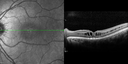

This pleasant 8-year-old child was seen in the office on March 8, 2012. He was examined for glasses and dilated examination showed retinal abnormalities.

VISUAL ACUITY: OD 20/40, OS 20/50. IOP: 12 OU. His lenses are clear.

OD: Vertical C/D ratio is 0.2. There are foveal cysts. There is also a retinal elevation inferiorly and there are patchy peripheral retinal hemorrhages.

OS: Vertical C/D ratio is 0.2. There are foveal cysts. There is peripheral retinal issues with some hemorrhage in some areas of peripheral retinoschisis.

SPECTRALIS-SD-OCT SCAN: The OCT scan does show foveal retinoschisis in both eyes. The average thickness of the macula in the right eye being 420 microns and the cysts appear to be forming predominately in the inner nuclear and inner plexiform layer. In the left eye the OCT scan shows an average central foveal thickness of 414 microns and the cysts in that eye are forming mostly in the inner plexiform inner nuclear layer. The peripheral line scans also show peripheral retinoschisis in both eyes outside the macula. It is a little bit closer in the right eye where the hemorrhage is and you can see vitreoretinal traction at the edge of the schisis cavity. (NOTE: Retinal thickness measured with Spectralis OCT is approximately 70 μm greater than that measured with Stratus OCT. This increased measurement corresponds to the inclusion of the outer segment-RPE-Bruch's membrane complex by Spectralis OCT.)